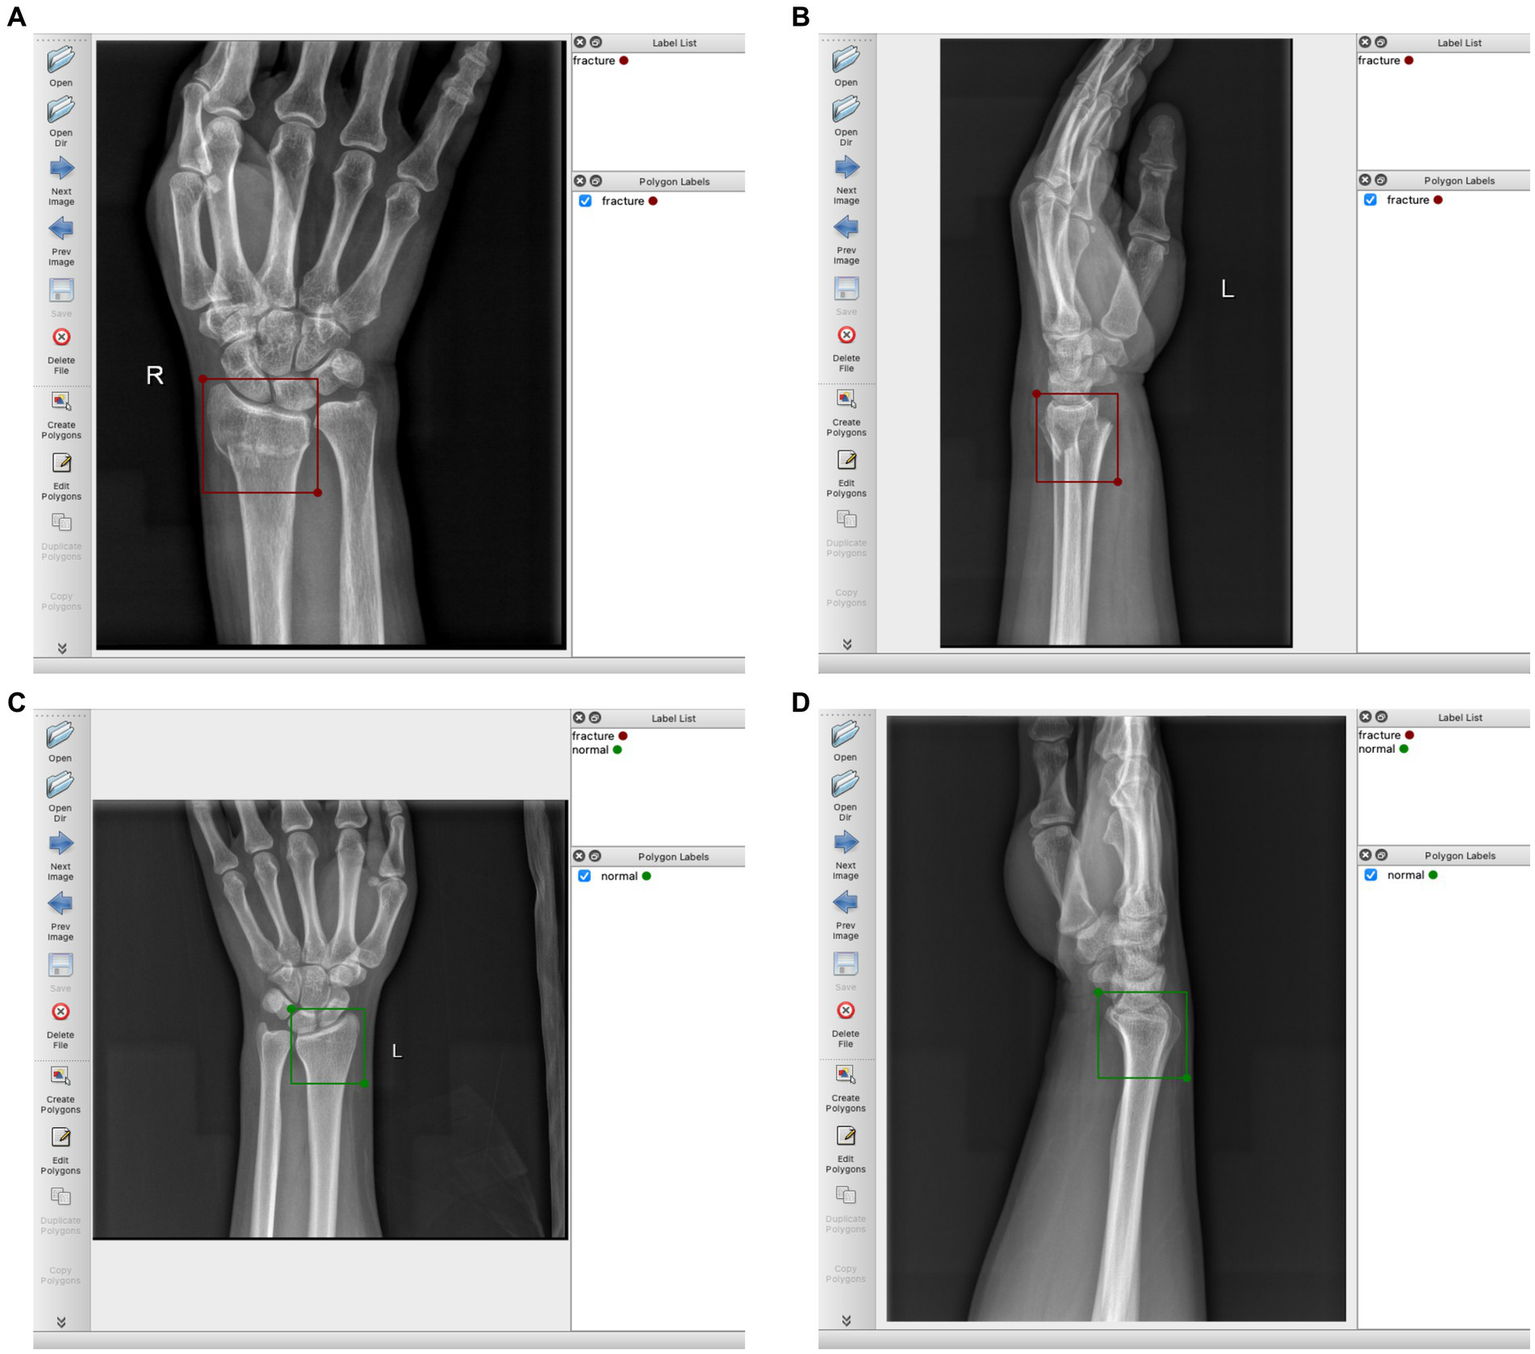

The region of the distal radius was drawn as a region of interest (RoI) using the rectangle tool, and was manually labeled according to the final imaging diagnosis (labels were divided into two categories: fracture and normal). We use the Labelme software package1 for manual labeling. Figure 2 provides a detailed illustration of our labeling process.

Figure 2

(A) Schematic diagram of labeling DRF AP radiograph, labeled as “fracture”; (B) DRF lateral radiograph, labeled as “fracture”; (C) Normal AP radiograph, labeled as “normal”; (D) Normal lateral radiograph, labeled as “normal”.